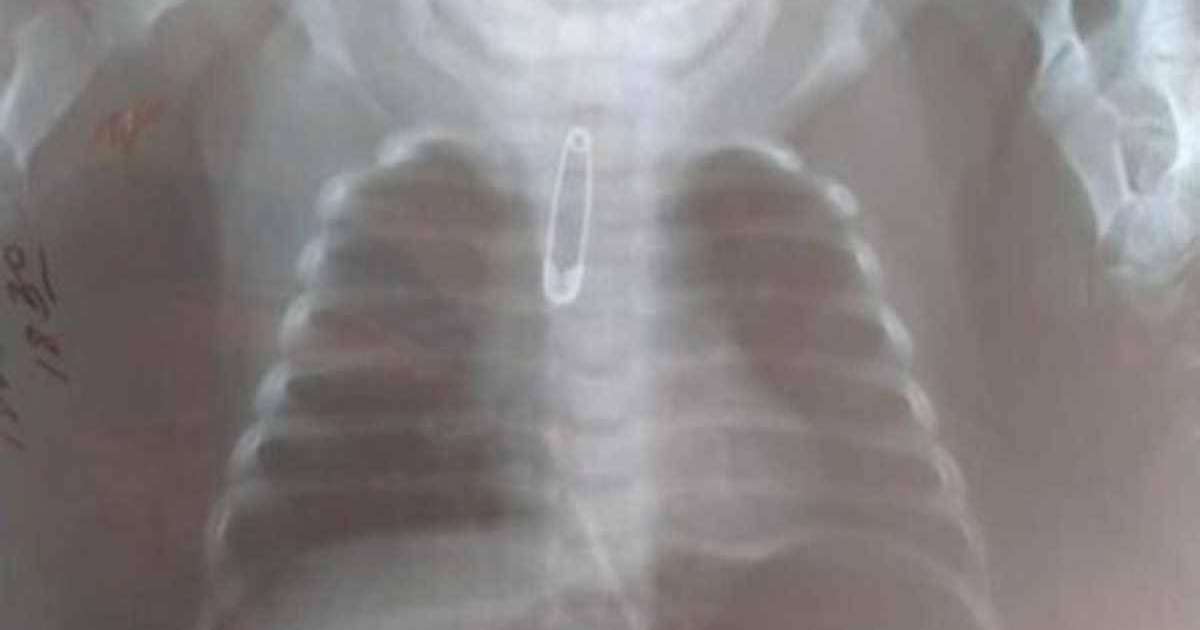

Шымкентте үш айлық баланың ішінен түйреуіш шықты

Шымкент қаласындағы балалар клиникалық ауруханасына тыныс алу жолында бөгде зат бар деген күдікпен үш айлық қыз баласы жедел жәрдем көлігімен жеткізілген. Бұл туралы Otyrar.kz басылы хабарлайды.

Нәрестені шұғыл түрде тексерген дәрігерлер рентгенограмма жасаған. Тексеру қорытындысында трахеяның жоғарғы үштен бір бөлігінде түйрегіш анықталды.

Баланың ішіндегі қауіпті затты алып шығу үшін ауруханадағы білікті хирургтар А.Тулкибаев, Н.Қоянбаев және анестизиолог дәрігері Б.Тотиков шұғыл түрде операция жасаған.

"Ота кезінде фибробронхоскоп аркылы кіріп, іштегі түйрегішті алып шықтық. Операция тіліксіз өтті. Баланың жалпы жағдайы жақсы, емдеу хаттамасына сәйкес қажетті ем алуда", - дейді ота жасаған дәрігер А.Түлкібаев.